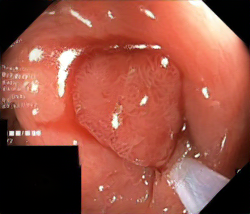

We have used a polyp dataset published with HyperKvasir dataset [51], which consists of polyp findings extracted from endoscopy examinations. HyperKvasir contains polyp images with corresponding segmentation masks annotated by medical experts. We use only this polyp dataset as a case study because of the time and resource-consuming training process of the SinGAN-Seg pipeline. However, the SinGAN-Seg model and pipeline can be used for any segmentation dataset.

A few sample images and the corresponding masks of the polyp dataset in HyperKvasir are shown in Fig 2. The polyp images are RGB images. The masks of the polyp images are single-channel images with white () for true pixels, which represent polyp regions, and black () for false pixels, which represent clean colon or background regions. In this dataset, there are different sizes of polyps. The distribution of polyp sizes as a percentage of the full image size is presented in the histogram plot in Fig 3, and we can observe that there are more relatively small polyps compared to larger polyps. Additionally, a subset of this dataset was used to prove that the performance of segmentation models trained with small datasets can be improved using our SinGAN-Seg pipeline, and the whole dataset was used to show the effect of using SinGAN-Seg generated synthetic images instead of a large dataset which has enough data to train segmentation models. In this regard, this dataset was used for two purposes: